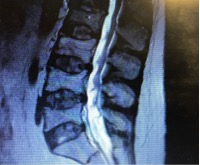

However, if you have Brittle Asthma (Like me) or Asthma that is difficult to control, many people call it different things… then you might be on what is called a “maintenance” dose of steroids, this is something you would take every morning despite whether you were having an exacerbation or not… I started having to take steroids everyday back in 2013 where I started on 7.5mg this very quickly got increased to 10mg and then again shortly afterwards was increased to 20mg after many hospital admissions in between… My last hospital admission my respiratory consultant increased my maintenance dose to 25mg… anyway my point is… (yeah Hayley get to it) in 4 years these steroids have done some serious damage to my bones despite regular DEXA Scans and calcium / Vitamin D supplements I have just been diagnosed with Osteoporosis and have multiple wedge fractures in my lower back I’ve also lost 2″ in height… (Below is part of my MRI scan)

These were found accidentally during a recent admission into hospital with yet another exacerbation of my brittle asthma, I’m lucky enough to have a very patient respiratory consultant who took my complaints of horrendous back pain seriously and once my chest was more stable, ordered every scan under the sun (Ultrasound / CT / MRI) all of which I had to lay on my back which was excruciating, anyway except the ultrasound – all the other scans revealed I had multiple wedge fractures in my back… but how? I hadn’t fallen over or damaged my back in any way (you’d think you’d remember) I was then diagnosed with steroid induced osteoporosis… OUCH!!